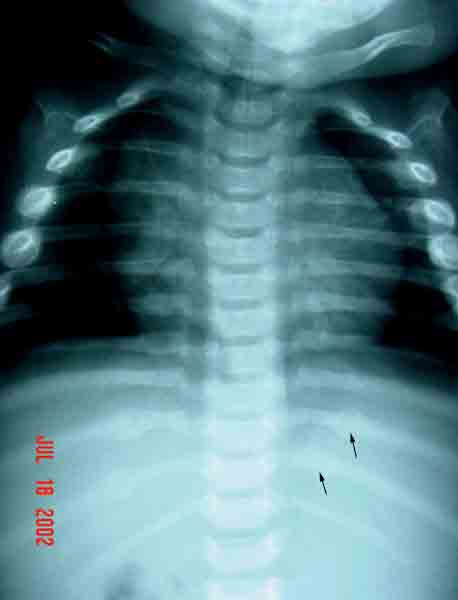

Left: Inflicted rib fractures in a 9-month-old child. Note the callus formation. Right: The same child 2 weeks later (in protective custody). Note the two new calluses.

This emphasizes the need for a repeat skeletal survey 2 weeks after the first.

(Photos courtesy of Children’s Hospital Boston Child Protection Team.)